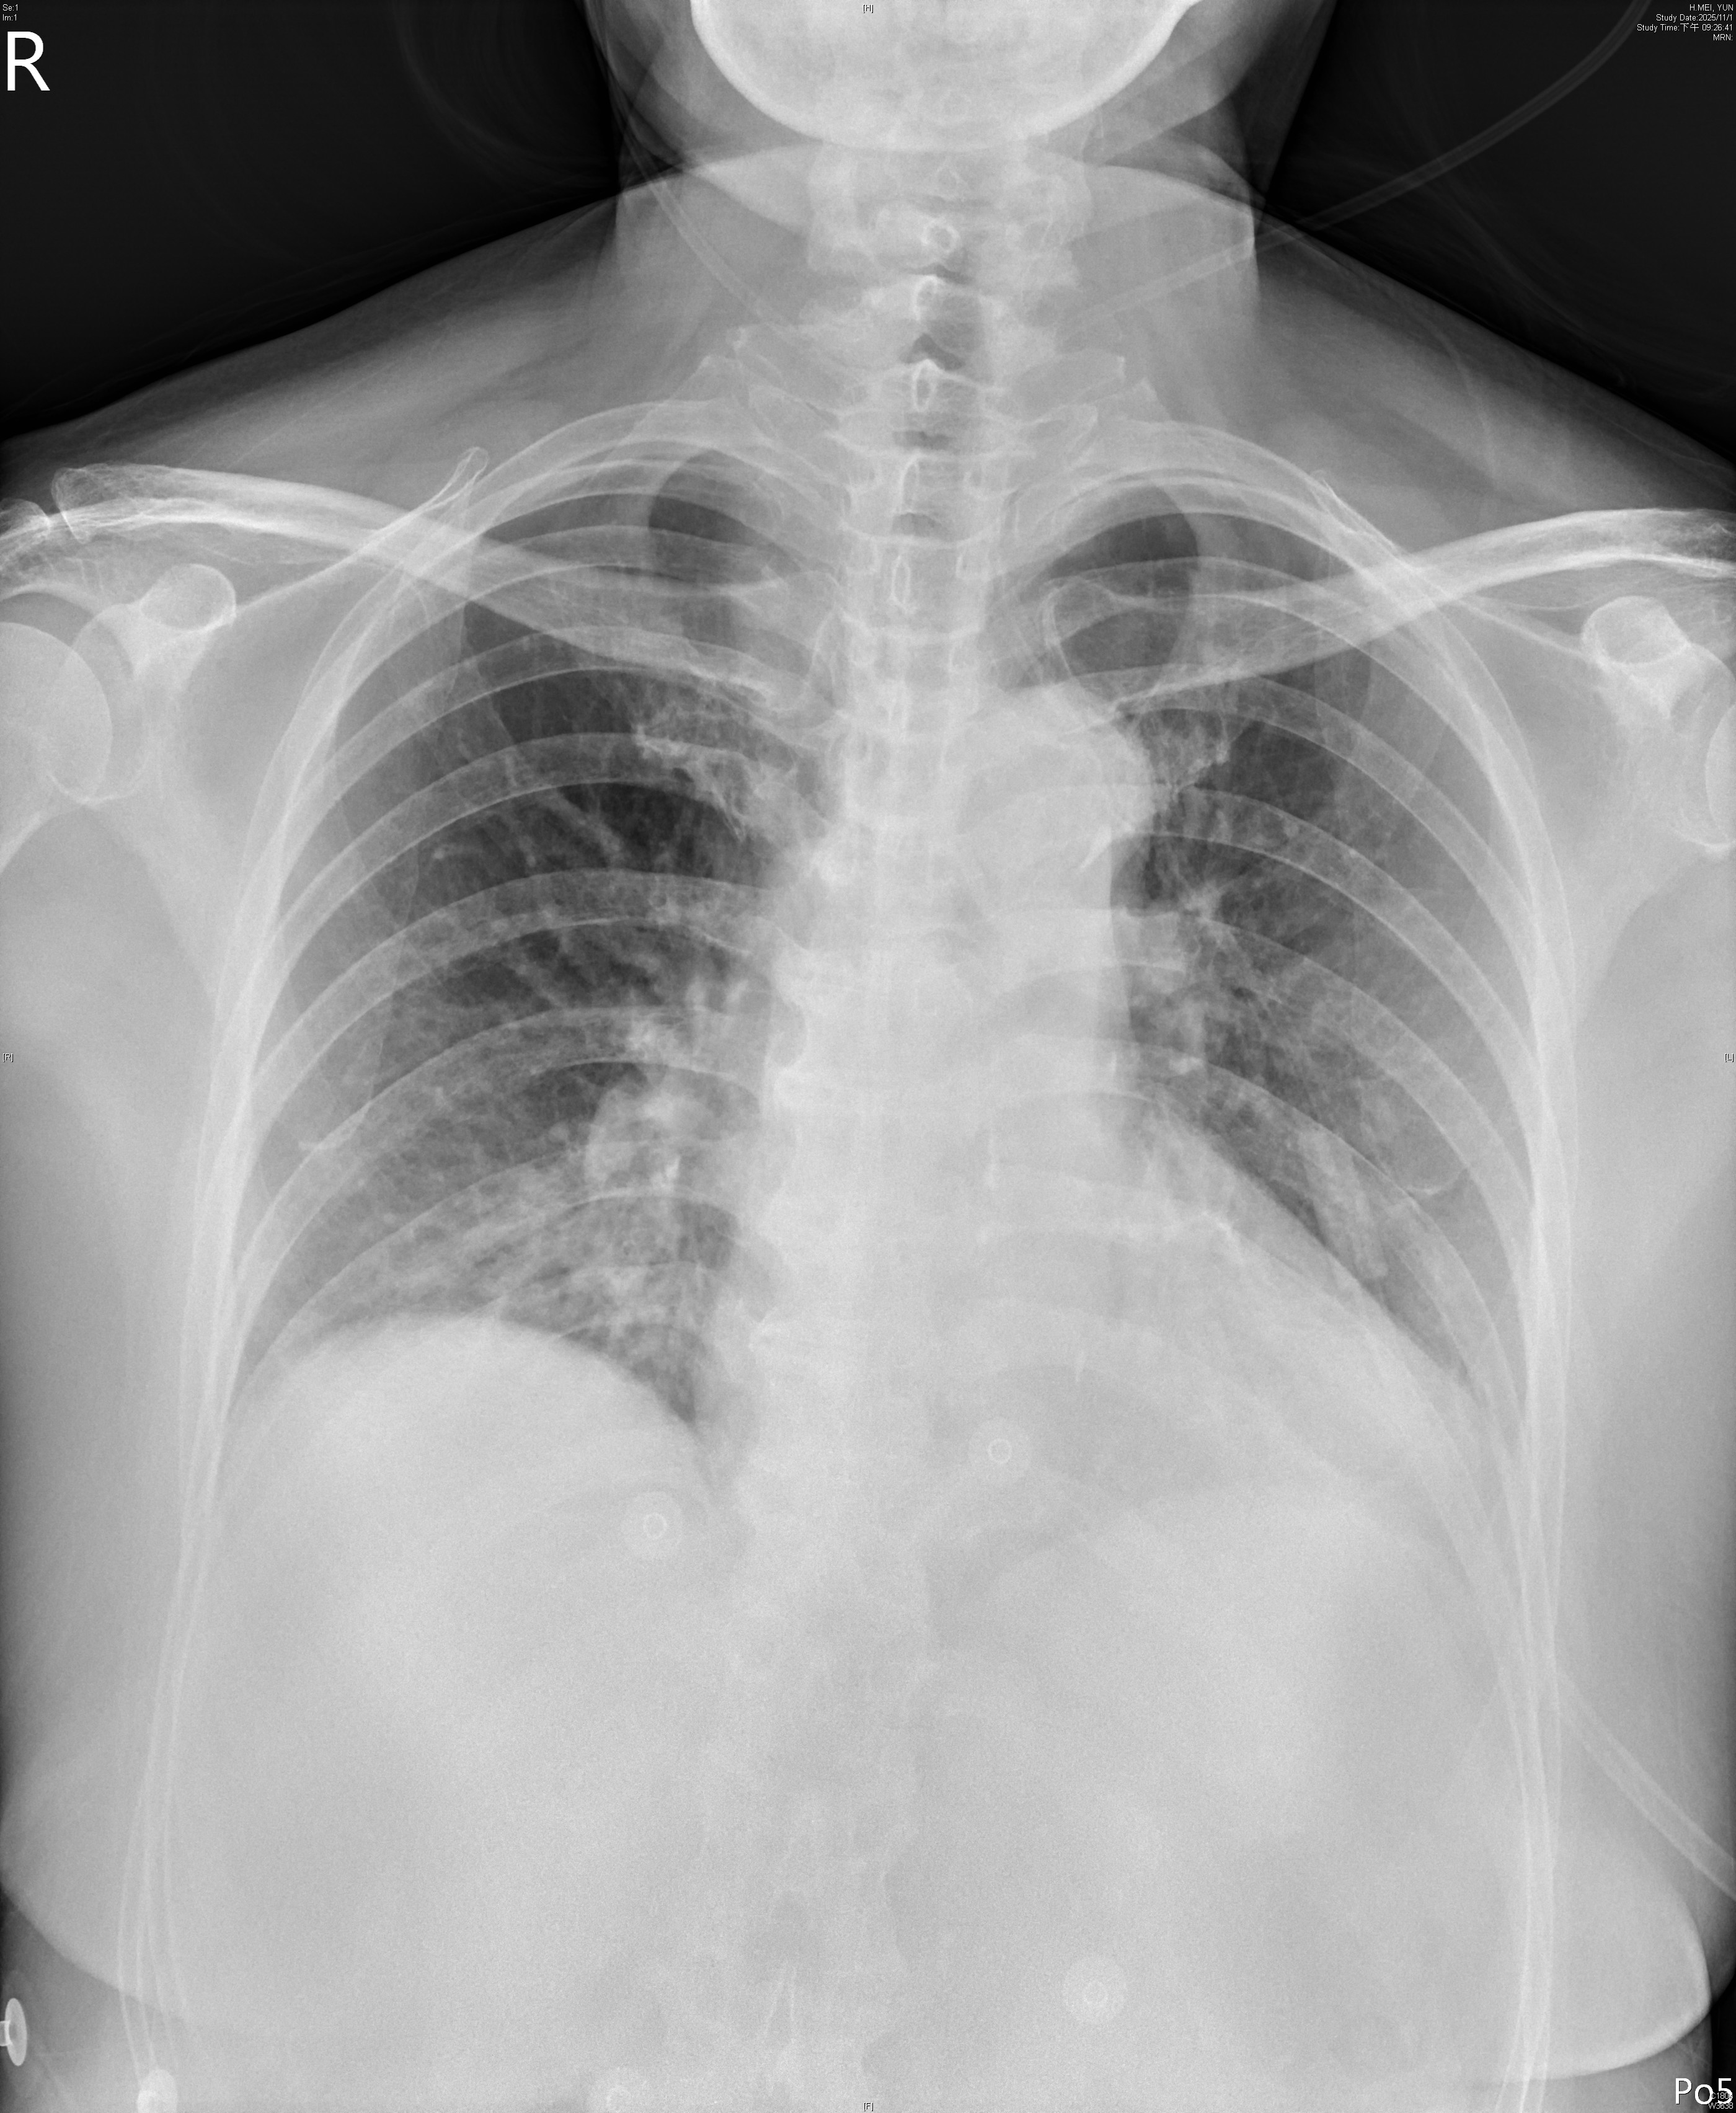

Electrocardiogramdemonstrated ST elevation in leads II, III, and aVF, with Q waves in lead III,indicating acute inferior myocardial infarction. Chestradiographshowed borderline cardiomegaly and mild pulmonary congestion